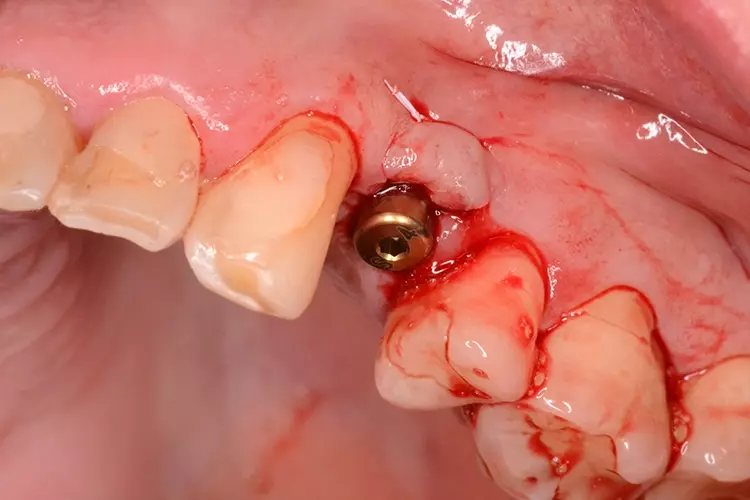

Bei dem heute 49-jährigen Patienten wurde seit Kindertagen versäumt, die Ober- und Unterkieferzahnbögen kieferorthopädisch auszurichten. Der Patient leidet seitdem stark unter seinen Zahnfehlstellungen.

Die Fraktur des stark elongierten Zahnes 21 war für den Patienten der Ausgangspunkt, sowohl die Front des Ober- als auch des Unterkiefers prothetisch überarbeiten zu lassen. Dabei wurde der frakturierte Zahn 21 durch ein navigiert eingesetztes Sofortimplantat ersetzt, während die verschachtelt stehenden Zähne 12 und 42 durch eine Brückenversorgung korrigiert wurden (Abb. 4a-j).